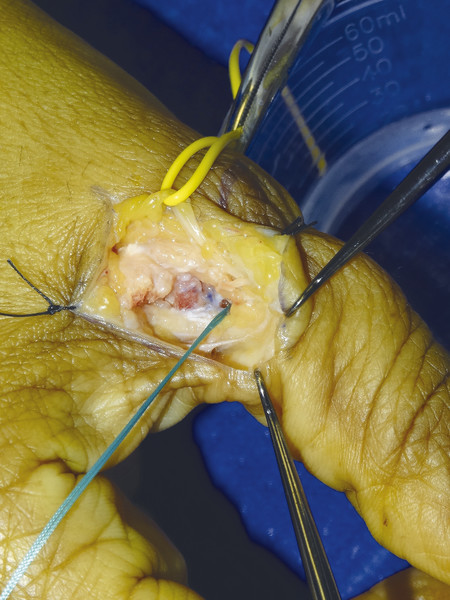

Fig. 10.10 Stener lesion with proximal end of UCL visible over adductor aponeurosis.

Fig. 10.15 Small bony segment avulsed off proximal phalanx, bony segment is removed before fixation with Mitek mini anchor onto the proximal phalanx.

Fig. 10.17 Mitek mini anchor fitted into bone and 2.0 Ticron used to pass through UCL as a half-modified Kessler suture.

Fig. 10.18 Final repair.